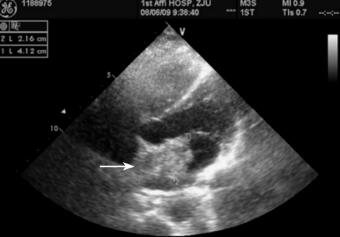

患者曾于2011年4月25日行普通心电图检查示“窦性心律”;2011年4月27日行24小时动态心电图示:窦性心律,偶发房性期前收缩。于4月27日行颈部血管彩超示“两侧颈动脉血流未见异常”。行超声心动图(2011年4月27日)示:左房房间隔水平见一大小约21.6mm×41.0mm中等回声团,提示黏液瘤可能性大;二尖瓣轻度反流(图3)。

图3 2011年4月27日行超声心动图检查,示左房房间隔水平见一大小约21.6mm×41.0mm中等回声团(箭头),提示黏液瘤可能